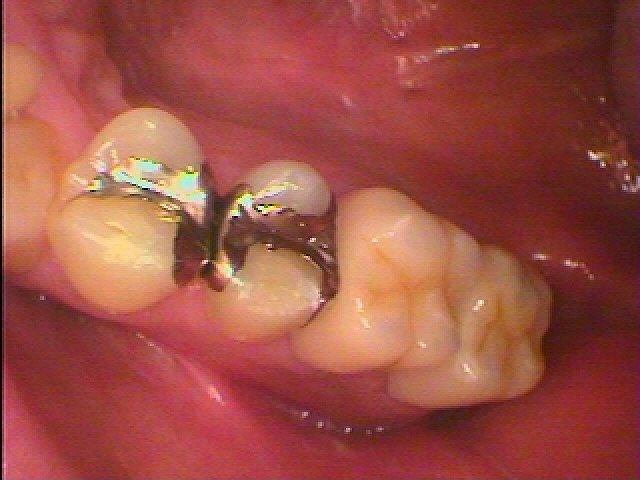

8番は抜歯、7番を何とか根の治療して残していきます

このようにファイバーコアにて支台築造を行っています